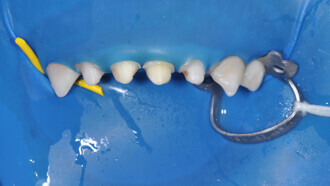

The Inman Aligner: Alignment, bleaching and bonding—A progressive approach to smile design (Part II)

The following article is Part II in a series discussing the use of the Inman Aligner as a tool for MICD.1 The first article (published in cosmetic dentistry...